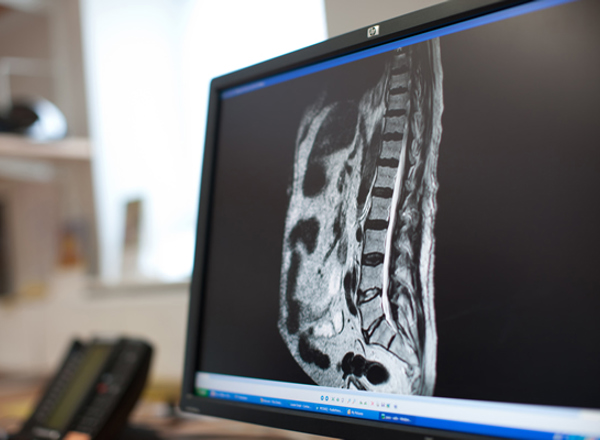

Spinal cord compression: what it means and how it can be treated

Spinal cord compression is pressure on the spinal cord and its nerves. This may happen if the bones are affected by cancer.